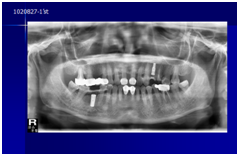

患者陳先生於91/06/03初診,為一個牙周病患者,合併有右下缺牙。經過保守性牙周處理後,於91/08/14放置右下三顆植體。

完成後大約半年至一年進行一次例行性追蹤檢查,並無特別問題。以下為96/08/13時的追蹤小片,可以見到當時三顆植體的骨高度並無顯著變化。但右下第一小臼齒此時發現有搖動度增加的情形,當時對該顆牙做了咬合調整,降低咬合功能負荷,希望能有所改善。

患者之後於96/11/08在右下第一小臼齒與植體間有膿胞產生,並於97/02/21確認右下第一小臼齒有根裂的情形,因此在97/02/29拔除此牙;經過將近半年後,於97/09/23放置一顆植體於此位置